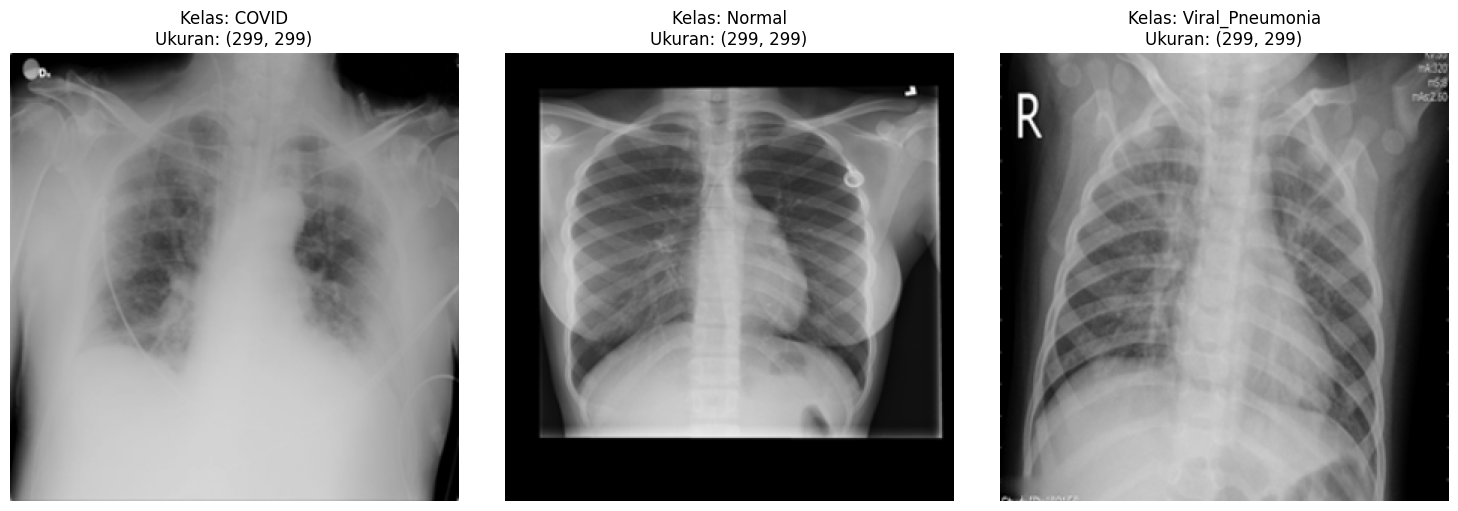

Multi-class Chest X-Ray Samples

Visual Ambiguity: Kemiripan tekstur (infiltrat/bercak) antara COVID-19 dan pneumonia biasa seringkali menyulitkan diagnosa manual dan rentan human error.

Eksklusi Lung Opacity: Kelas ini dihapus dari dataset Kaggle karena hanya temuan radiologis umum, bukan penyakit spesifik. Menghapusnya menajamkan decision boundary model.